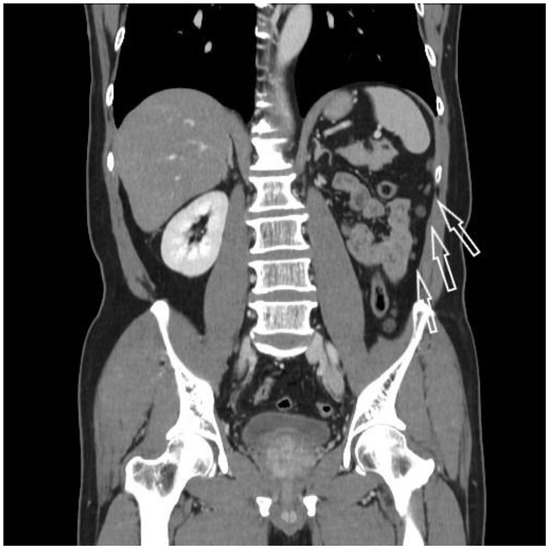

2. Case Report